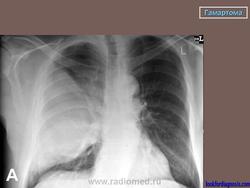

Гамартома

Приложения:

1.gpm_.2_582.jpg2.gam_.3_505.jpg3._gam.4_406.jpg